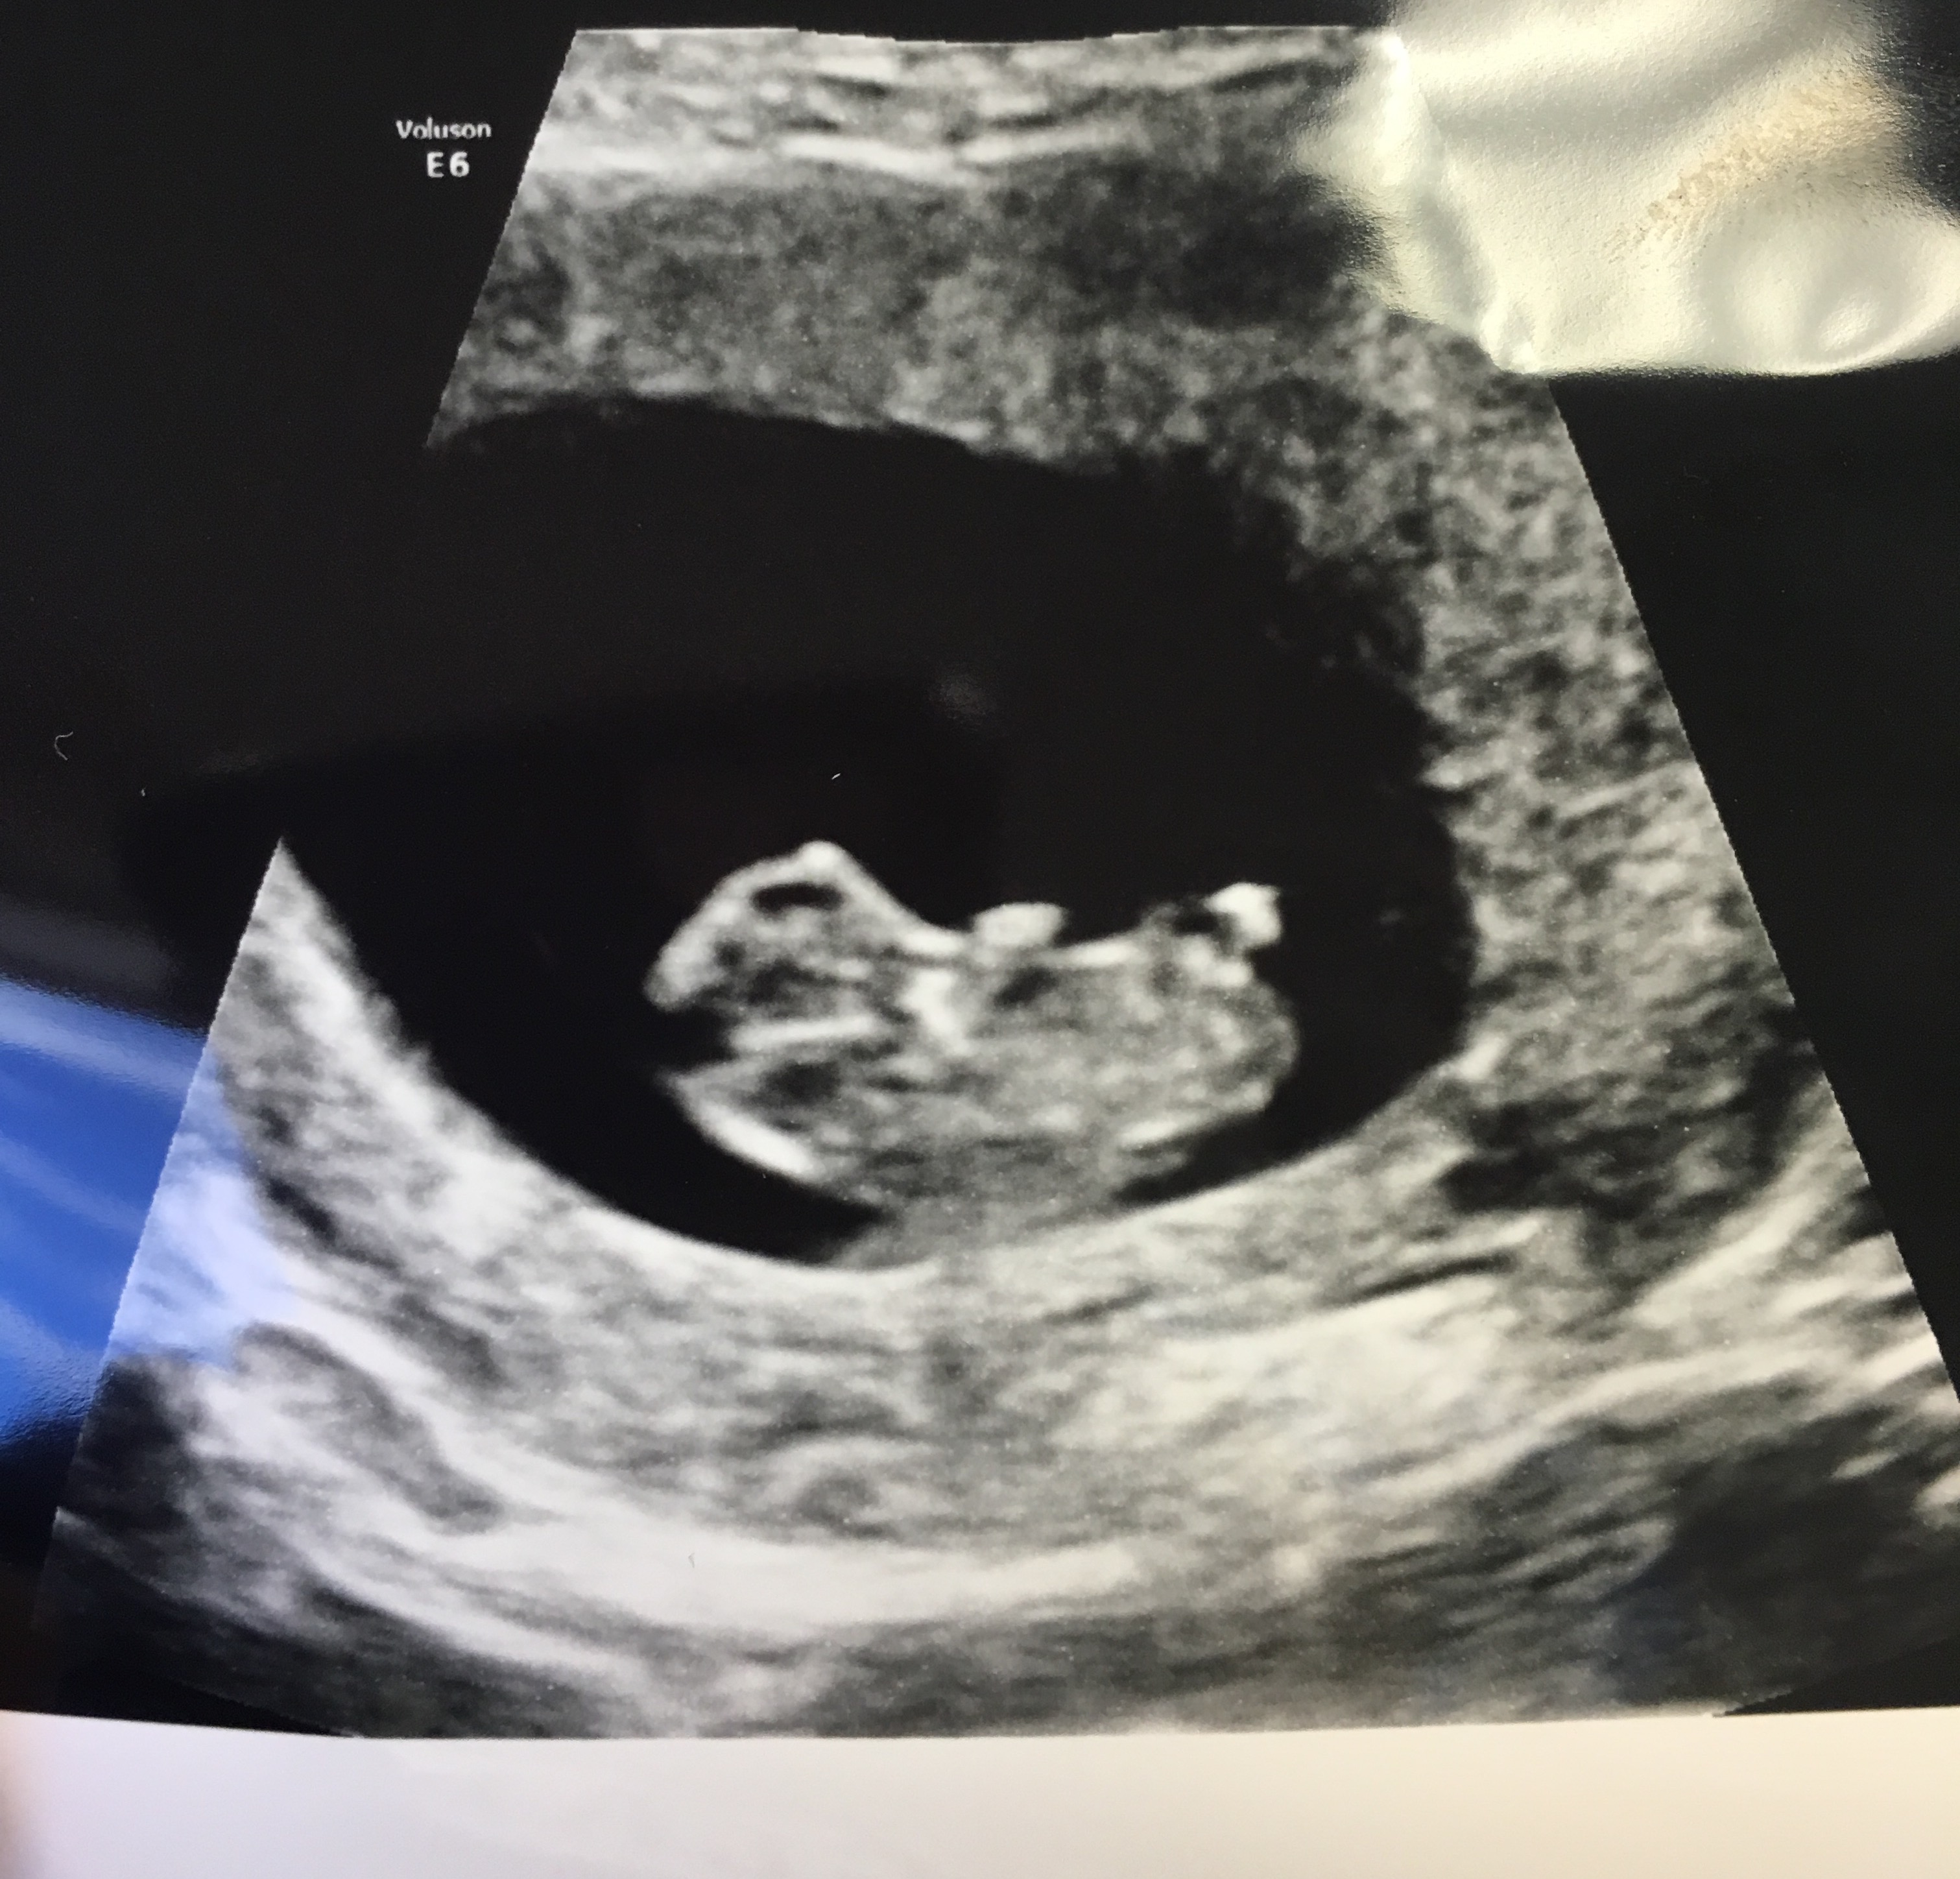

too early!

way too early

Cute little bub :) Too early for nub guessing at 12 - 13 weeks (13w is best). Also too late for a Ramzi guess.